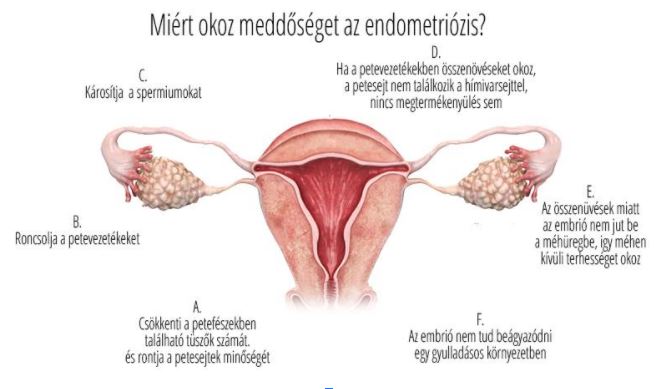

A méh nyálkahártyáját, az úgynevezett endometriális sejtek alkotják, mely, ha nem ágyazódik be embrió, hormonális hatásra leválik, és a nő menstruál.

A méh nyálkahártyáját, az úgynevezett endometriális sejtek alkotják, mely, ha nem ágyazódik be embrió, hormonális hatásra leválik, és a nő menstruál.